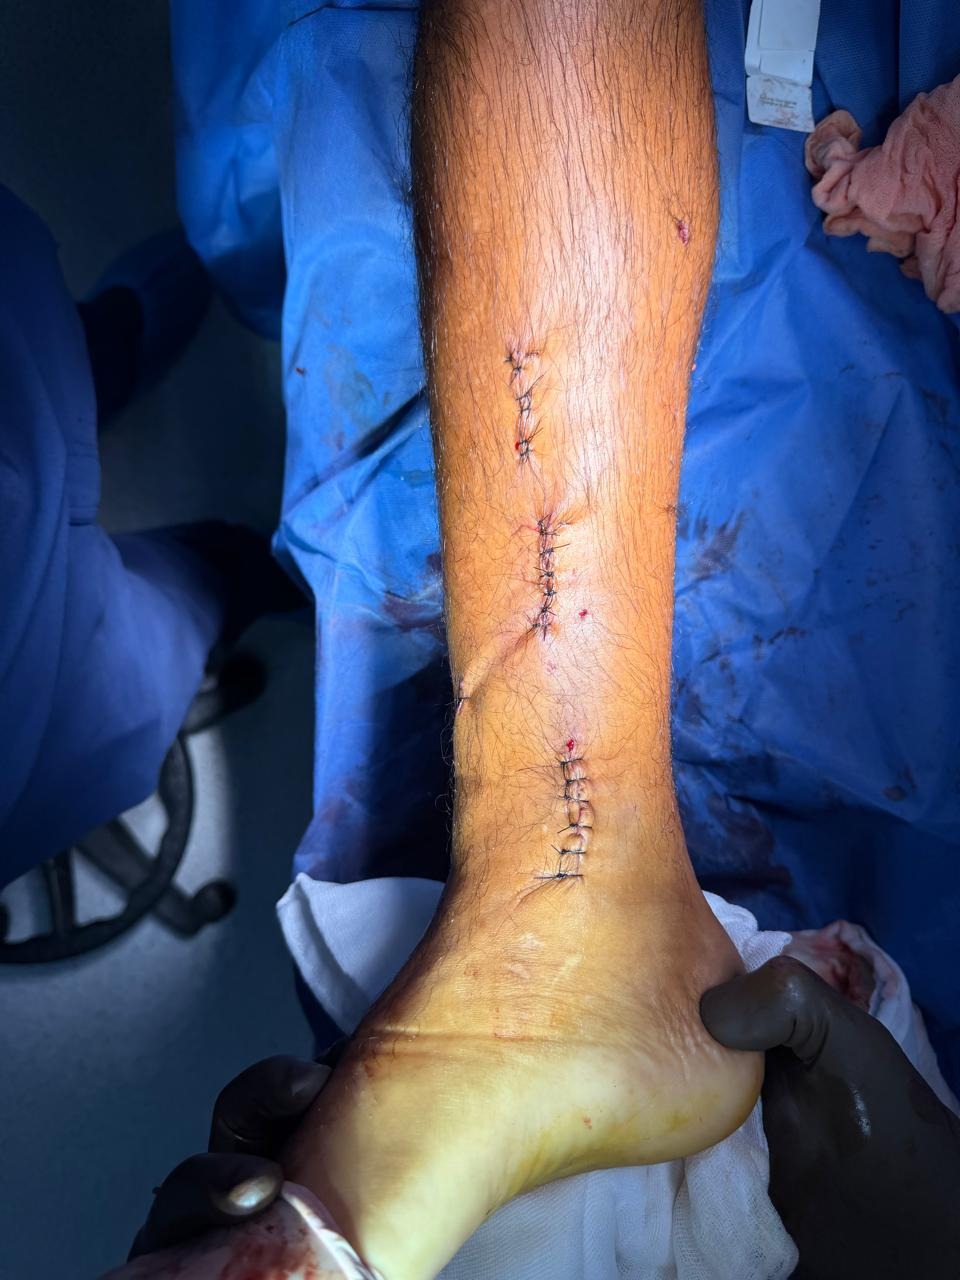

My name is Rafael Benson Arellano. I’m a local resident and small business owner working alongside my brothers in our family business. Recently I was involved in a serious motorcycle accident that left me with a broken leg and required emergency surgery and hospitalization in La Paz.